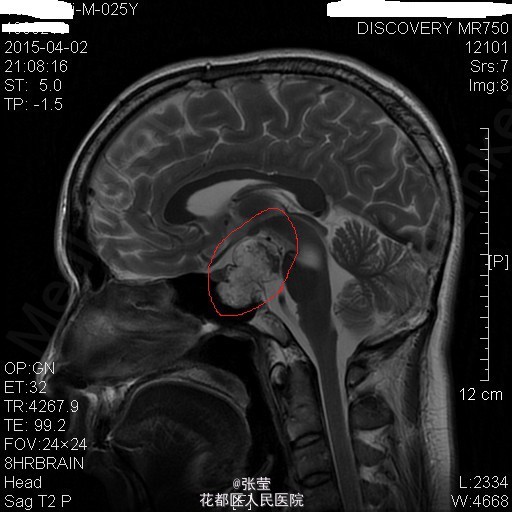

青年男性,主诉:头晕伴肢体乏力1周。 现病史:患者1周前始无明显诱因反复出现头晕,伴左侧肢体乏力、行走不稳,偶伴头痛、恶心感,休息后可稍缓解,无呕吐,无天旋地转感,无晕厥,无伴听力、记忆力减退等,发作无明显规律。至当地医院就诊,头部MR结果示:右间脑下方-脑干-桥前池-左鞍底区肿瘤,并瘤内卒中。

查体:神清,对答切题,双瞳等大等圆,直径约3mm,对光反射灵敏,双侧听力粗测正常,四肢肌力Ⅴ级。生理反射存在,病理征未引出。 辅查:颅脑MR:1、斜坡区占位,侵及中脑、脑桥右份及蝶窦,病灶ADC值增高,FA值下降,考虑脊索瘤并囊变、出血可能大。 2、MRA示双侧颈内动脉向外侧移位,余脑动脉未见明确异常。